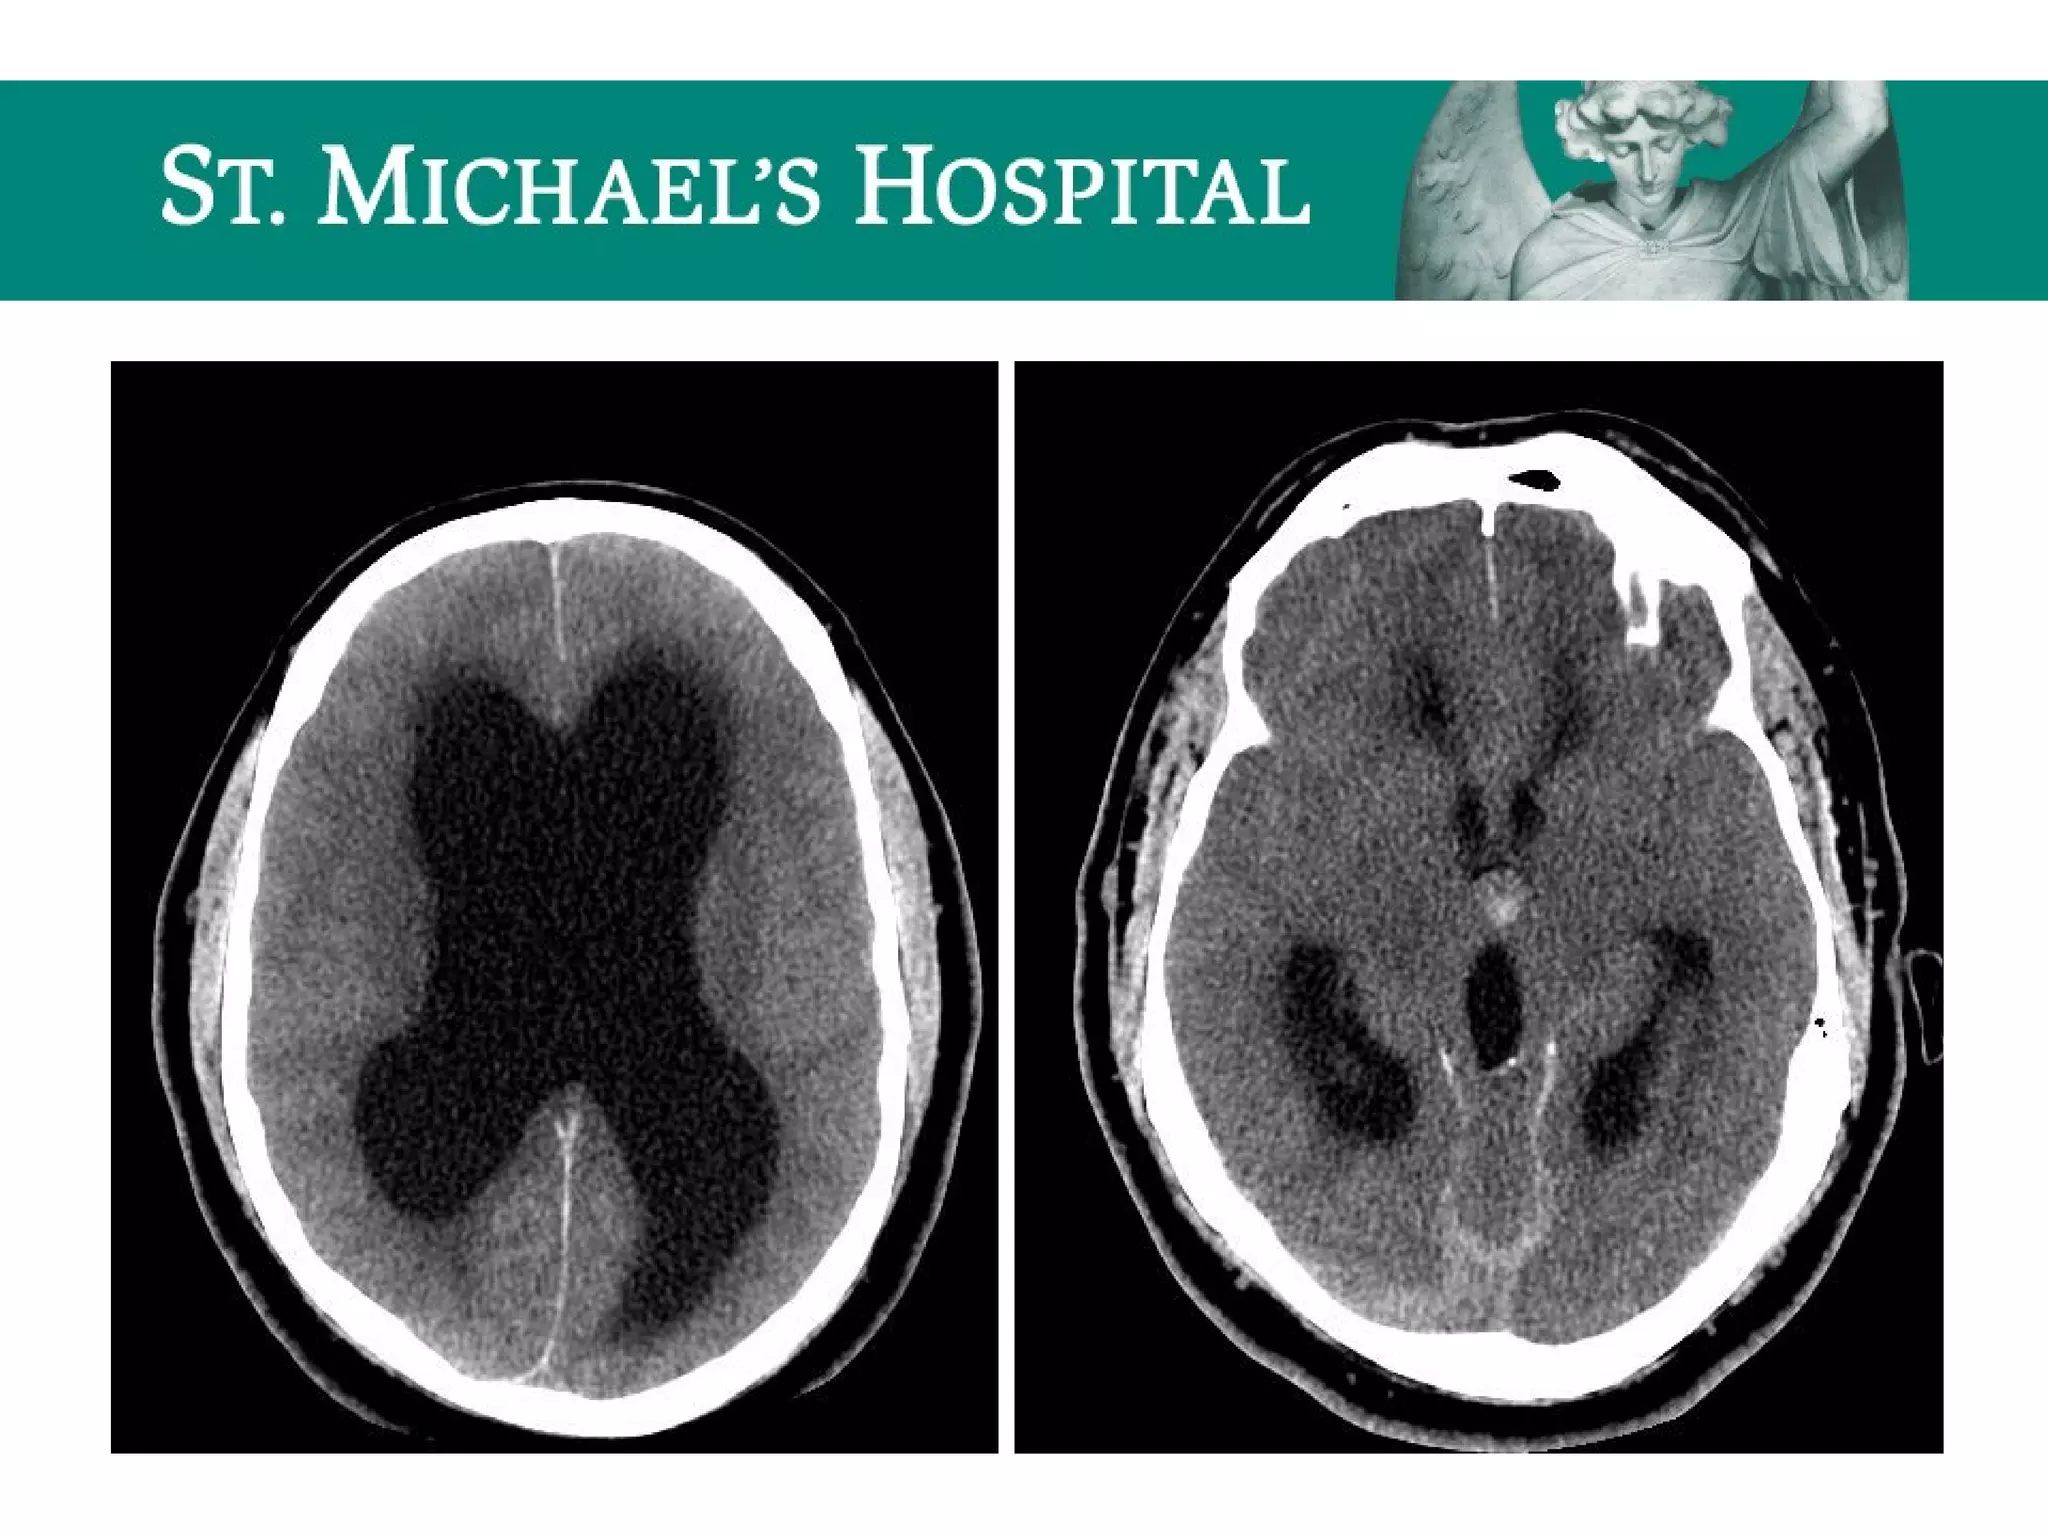

Communicating Hydrocephalus

 Blockage of CSF flow over the cerebral convexities/absorption at the arachnoid

granulations secondary to:

– SAH, meningeal mets, granulomatous meningitis

 Rapid CSF production

 eg. choroid plexus papilloma

 Radiological features:

 Symmetrical enlargement of the lateral, third and fourth ventricles

 Normal/effaced cerebral sulci

 Dilatation of subarachnoid cisterns

 Periventricular low attenuation  transependymal flow of CSF

Non-communicating Hydrocephalus

 Location of obstruction/causes:

 Lateral ventricles  ependymoma, meningioma

 Foramen of Monro  third ventricular colloid cyst

 Aqueduct of Sylvius  congenital aqueductal stenosis, IVH

 Fourth ventricle/foramen of Luschka and Magendie  congenital, tumour,

extrinsic compression

 Ventricular dilatation proximal to the level of obstruction

 Earliest indication may be dilatation of the temporal horns

 Progressive enlargement of the ventricular system which is disproportionate

to narrowed and effaced cortical sulci

 Periventricular low attenuation (transependymal CSF flow)

Communicating Hydrocephalus  Blockageof CSF flow over the cerebral convexities/absorption at the arachnoid granulations secondary to: – SAH, meningeal mets, granulomatous meningitis  Rapid CSF production  eg. choroid plexus papilloma  Radiological features:  Symmetrical enlargement of the lateral, third and fourth ventricles  Normal/effaced cerebral sulci  Dilatation of subarachnoid cisterns  Periventricular low attenuation  transependymal flow of CSF

Non-communicating Hydrocephalus  Locationof obstruction/causes:  Lateral ventricles  ependymoma, meningioma  Foramen of Monro  third ventricular colloid cyst  Aqueduct of Sylvius  congenital aqueductal stenosis, IVH  Fourth ventricle/foramen of Luschka and Magendie  congenital, tumour, extrinsic compression  Radiological features:  Ventricular dilatation proximal to the level of obstruction  Earliest indication may be dilatation of the temporal horns  Progressive enlargement of the ventricular system which is disproportionate to narrowed and effaced cortical sulci  Periventricular low attenuation (transependymal CSF flow)